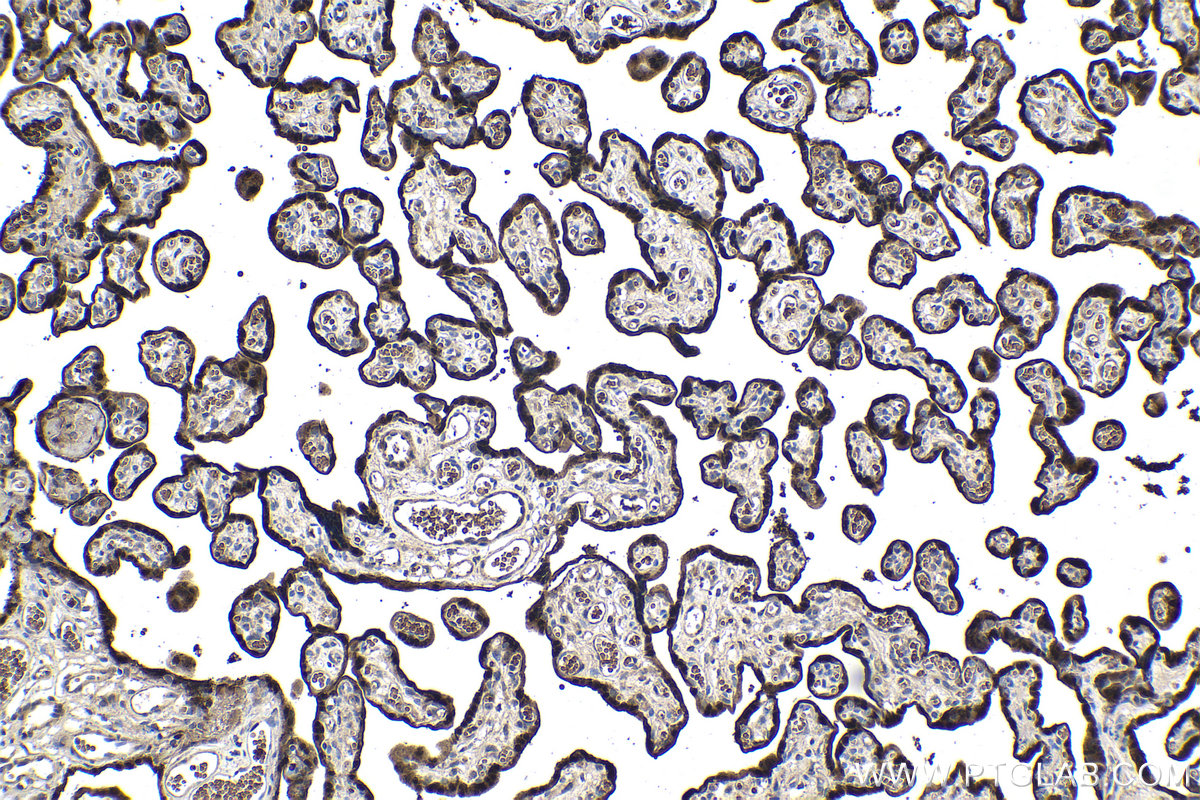

| Positive IHC detected in | human placenta tissue, mouse lung tissue Note: suggested antigen retrieval with TE buffer pH 9.0; (*) Alternatively, antigen retrieval may be performed with citrate buffer pH 6.0 |

FH Bénédicte (Verified Customer) (02-13-2026) | IHC staining of mouse colon after induction of colitis using 11419-1-AP Immunohistochemical analysis of paraffin-embedded mouse colon tissue (mouse subjected to colitis) using 11419-1-AP (HOPX antibody) at dilution of 1:200 (30x on NDPview). Heat mediated antigen retrieval with Tris-EDTA buffer (pH 9.0).